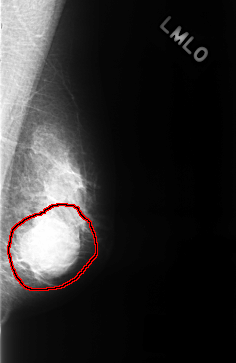

ics_version 1.0 filename C-0323-1 DATE_OF_STUDY 1 2 1995 PATIENT_AGE 48 FILM FILM_TYPE REGULAR DENSITY 4 DATE_DIGITIZED 8 10 1998 DIGITIZER LUMISYS LASER SEQUENCE LEFT_CC LINES 4528 PIXELS_PER_LINE 2984 BITS_PER_PIXEL 12 RESOLUTION 50 OVERLAY LEFT_MLO LINES 4352 PIXELS_PER_LINE 2824 BITS_PER_PIXEL 12 RESOLUTION 50 OVERLAY RIGHT_CC LINES 4448 PIXELS_PER_LINE 2848 BITS_PER_PIXEL 12 RESOLUTION 50 NON_OVERLAY RIGHT_MLO LINES 4384 PIXELS_PER_LINE 2784 BITS_PER_PIXEL 12 RESOLUTION 50 NON_OVERLAY |

FILE: C_0323_1.LEFT_MLO.OVERLAY TOTAL_ABNORMALITIES 1 ABNORMALITY 1 LESION_TYPE MASS SHAPE ROUND MARGINS OBSCURED ASSESSMENT 4 SUBTLETY 5 PATHOLOGY BENIGN TOTAL_OUTLINES 1 BOUNDARY |